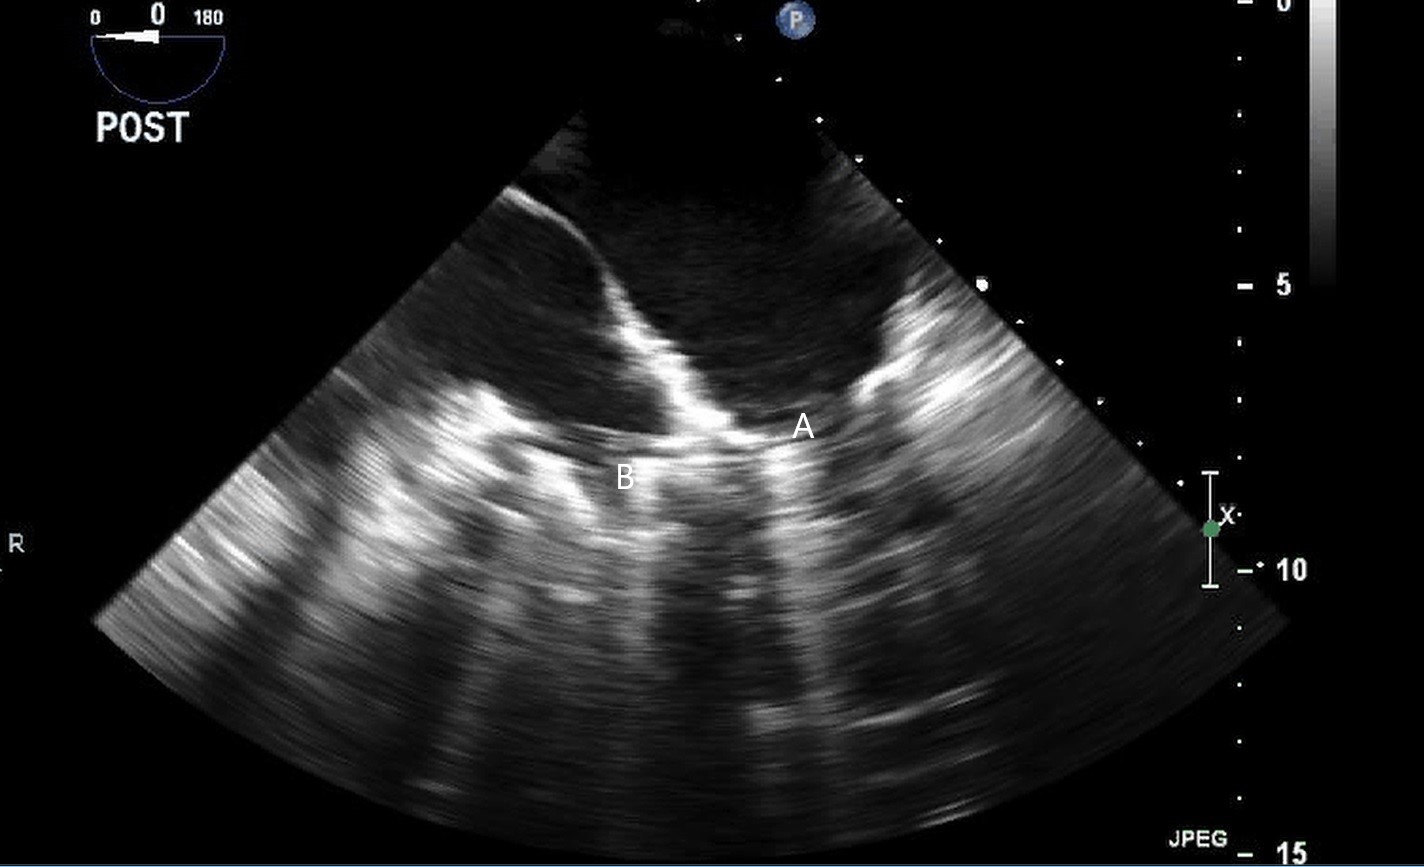

The intra-aortic balloon pump is a percutaneously placed counter pulsation device which helps in decreasing afterload as well as augmenting coronary perfusion. Initially developed in the 1960s it is the oldest MCS device and given its simplicity, cost effectiveness, and ease to implant and explant, it is the most commonly used temporary support device [6]. Although it is typically placed in the cardiac catheterization lab under fluoroscopic guidance, TEE can be utilized to help in its placement in the intubated patient in the intra-operative setting. The femoral artery is the most common site of placement however they can on occasion be placed in alternative sites such as the axillary artery or directly into the aorta [7, 8]. When placed via the femoral artery, it is threaded over a guidewire. TEE can be used to visualize both the guidewire as well as the tip of the IABP catheter during placement (Fig. 1) [9]. Ideal positioning of the balloon tip is 1–2 cm distal to the left subclavian artery to derive maximal hemodynamic benefit [10]. Positioning can be confirmed by visualizing the descending aorta and then withdrawing the TEE probe until the left subclavian artery and aortic arch are visualized. Upon activation of the balloon pump the gas filled balloon will cause shadowing and reverberation artifacts (Fig. 2). Its presence can be used as confirmation of proper function of the device. If these artifacts are not seen or bubbles are visualized in the aorta, rupture of the IABP should be suspected [9]. In addition to hemodynamic monitoring with a Swan-Ganz catheter, TTE can be used to monitor LV function after IABP placement and can help guide weaning of IABP support. It can also visualize any new or worsening aortic regurgitation. Given that IABPs work by reducing afterload, on rare occasions they can precipitate dynamic outflow tract obstruction and paradoxically worsen cardiogenic shock. Examples include patients with a relatively preserved basal or septal myocardial function in scenarios such as takotsubo cardiomyopathy or acute myocardial infarctions. Doppler imaging and color flow doppler can be used to identify such scenarios [11].

Fig. 1.TEE demonstrating IABP in descending aorta (A).

TEE demonstrating IABP in descending aorta (A) with reverberation artifact seen behind it upon activation (B).